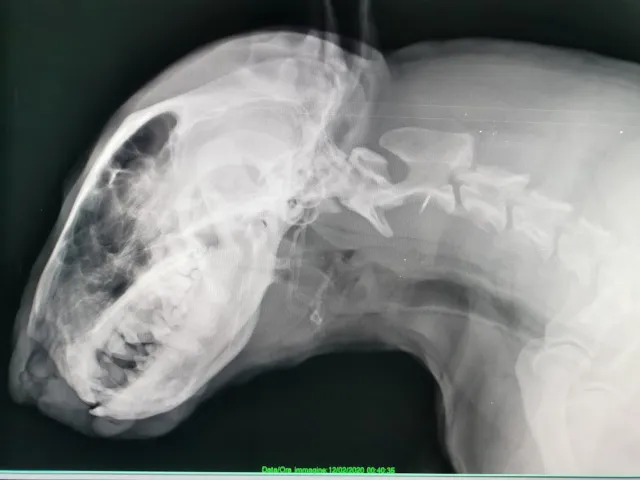

Diagnostica avanzata

Ecografie, radiologie digitali ed esami di laboratorio

Neurologia clinica

Diagnosi e trattamento delle patologie neurologiche

Odontoiatria veterinaria

Igiene orale e trattamenti dentali